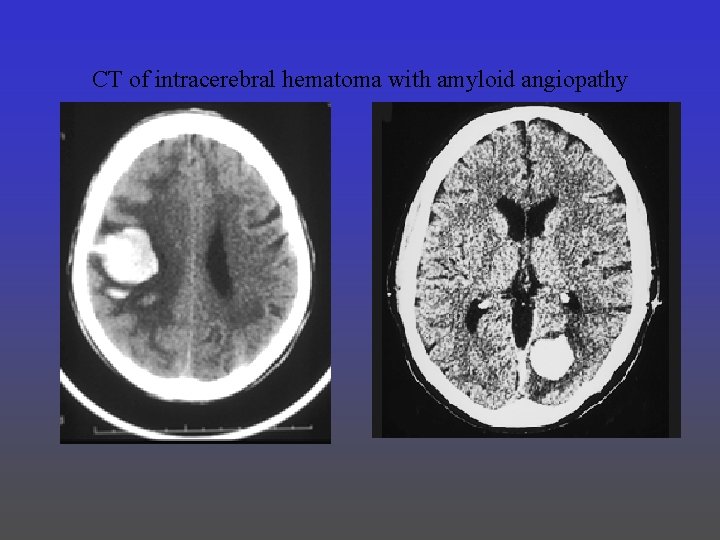

CT of intracerebral hematoma with amyloid angiopathy